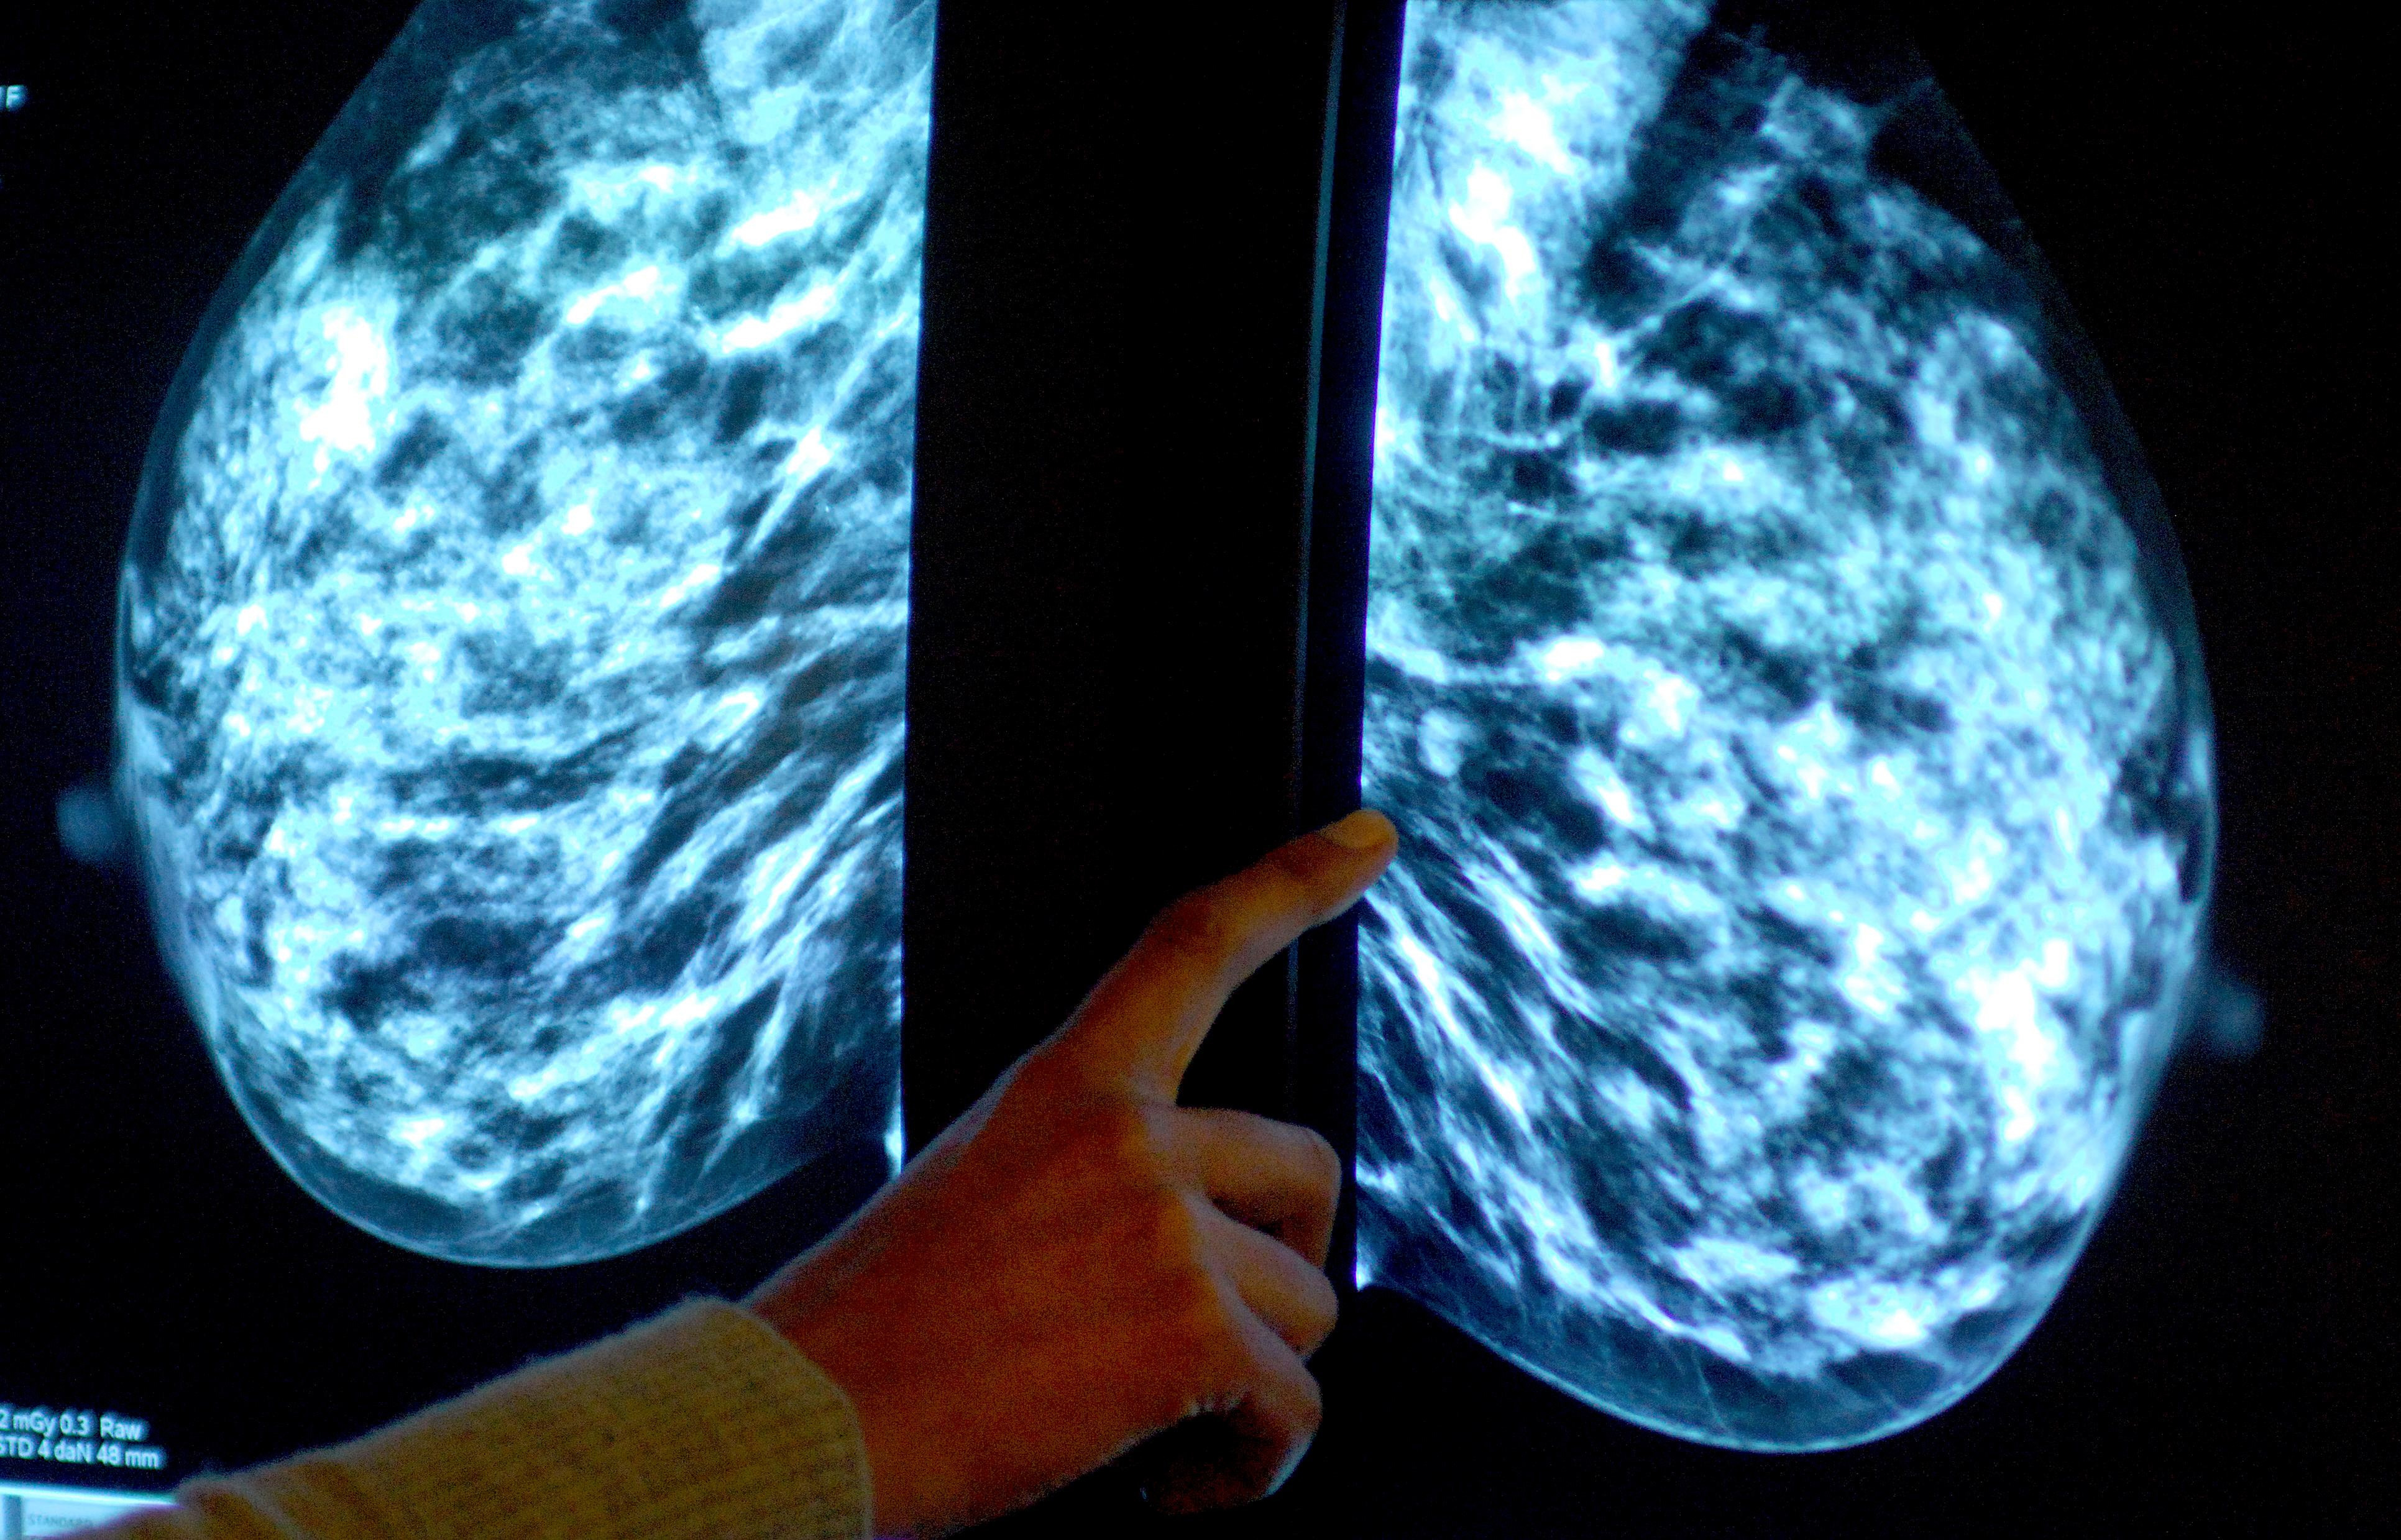

Breast screening uptake in Devon remains below pre-pandemic levels, new figures show.

Anyone registered with a GP as female will be invited for NHS breast screening every three years between the ages of 50 and 71.

NHS England figures show 47,240 of the 72,250 people invited for a screening in the former NHS Devon CCG had a test in the year to March this year.

It meant uptake of the screening stood at 65% – down from 69% the year before, and below pre-pandemic levels of 74% in 2019-20.